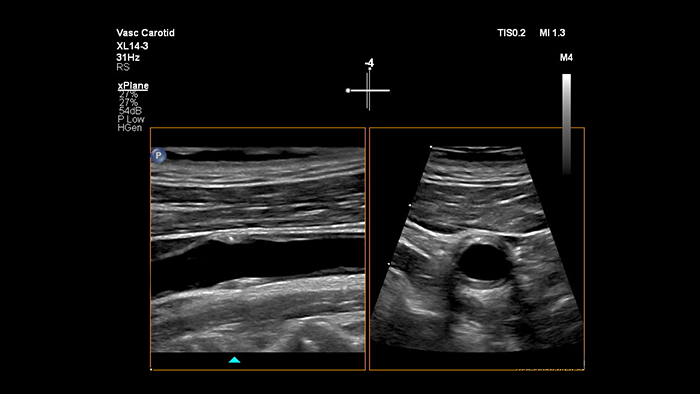

La sonde xMATRIX XL14-3 offre une imagerie xPlan qui va au-delà de l’approche conventionnelle des examens vasculaires, en fournissant des images en temps réel, simultanément dans des plans longitudinaux et transversaux. Atout majeur : avec l’imagerie xPlan, il n’est plus nécessaire de faire pivoter la sonde pour obtenir des vues orthogonales. Un simple mouvement de la boule de commande permet d’obtenir une évaluation anatomique complète, ce qui permet de gagner du temps lors de l’examen.

La sonde xMATRIX XL14-3 offre également les capacités du Doppler xPlan. Le Doppler pulsé xPlan permet un positionnement précis du volume d’échantillonnage du Doppler en utilisant des images de référence longitudinales et transversales. Atout majeur : Doppler xPlan réduit les erreurs de positionnement du volume d’échantillonnage. Il offre aussi une reproductibilité plus fiable et une meilleure cohérence lors de l’échantillonnage d’une sténose importante.